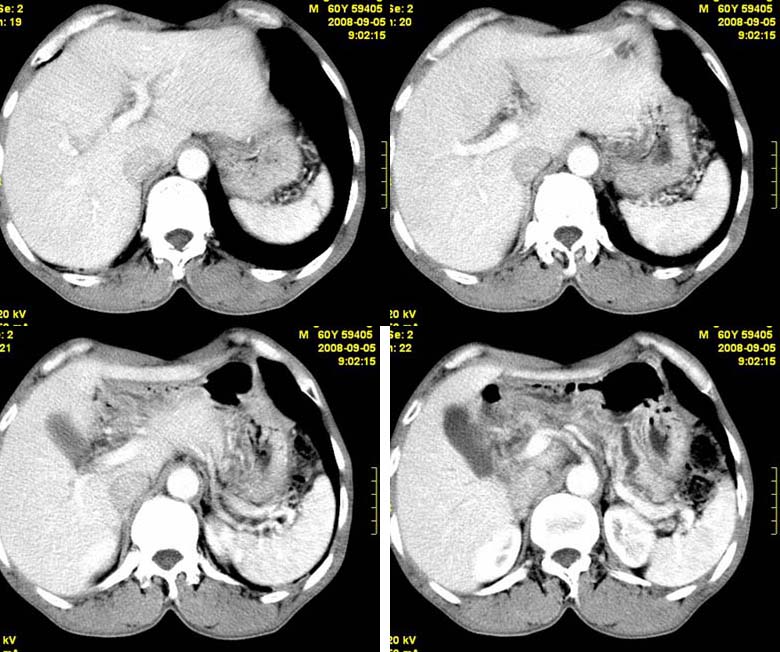

标题: CT15580:M60Y,胰腺病变,平扫+增强 [打印本页]

标题: CT15580:M60Y,胰腺病变,平扫+增强

患者,男, 60,既往有间歇腹痛病史多年,现右上腹痛,加重一月,伴右后背部疼痛,无黄疸,无发热。

胰头区增大,胰管明显扩张,不均匀强化,且与 周围结构不清,后背疼痛,考虑为胰腺头部胰腺癌。

胰头区增大,胰管明显扩张,不均匀强化,且与 周围结构不清,后背疼痛,考虑为胰腺头部胰腺癌。

同意胰头部囊腺癌

胰头囊样增大不均匀强化,腺管扩张。结合病史首诊慢性胰腺炎、假性囊肿